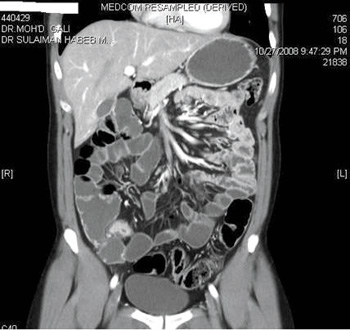

يعتمد تشخيص وفحص الأمعاء الدقيقة منذ زمن طويل على استخدام الأشعة التي ما زالت تستخدم حتى الآن، ولكن في الآونة الأخيرة طرأ الكثير من التطور على هذه الفحوصات والاستعانة بتقنيات جديدة في كل مرة، حتى تم استخدام الكبسولة التشخيصية للجدار الداخلي للأمعاء إلا أن الأشعة ظلت مهمة جداً في هذا المجال.